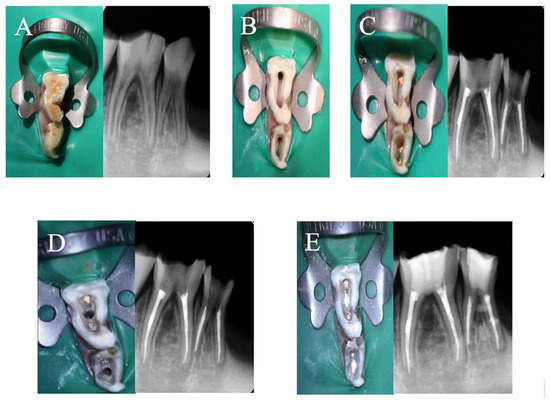

The procedures were all performed by one operator. The goats were continuously monitored for any changes in habits and food intake during the post-treatment evaluation periods. The clinical steps and radiographic images were documented in one animal for illustration purposes (Figure 2).

Figure 2. Clinical photographs and radiographic images of (A) pre-operative, (B) access opening, (C) obturation, (D) furcation induction, (E) perforation repair.